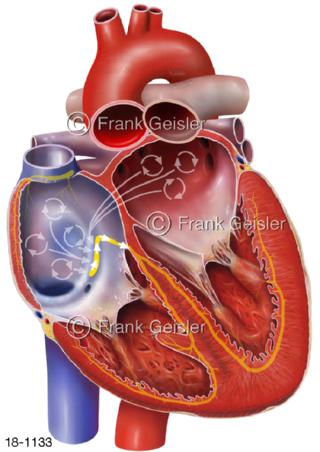

18-1133 Herz Vorhofflimmern Atrium, Herzrhythmusstörung